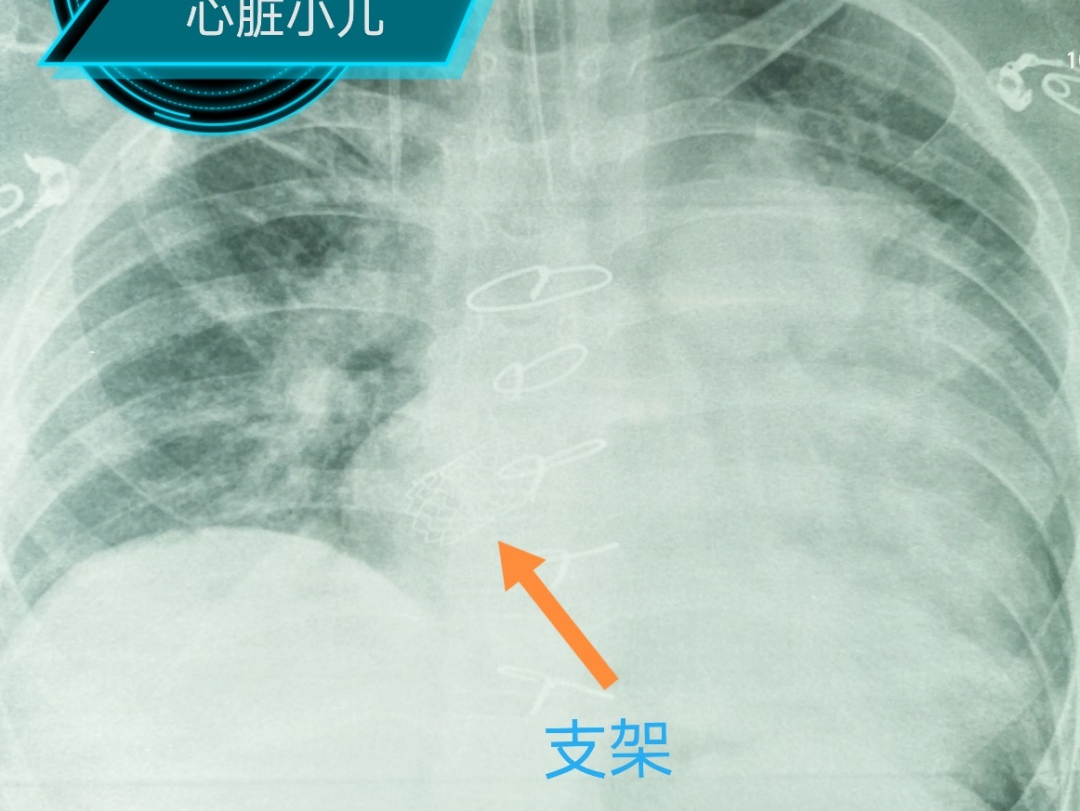

2020年全球第一个肺动脉支架Pul-Stent®,由中国企业研发成功并在国内率先获批上市。陈国良副主任医师也相继成功运用该支架,对几例肺动脉狭窄病人实施了支架植入。Pul-Stent®肺动脉支架小巧的外径、强大的支撑力及优秀的柔顺性给他留下了深刻的印象,同时也给他带来灵感:如果在肺静脉板障狭窄部位植入支架,那么肺静脉淤血就迎刃而解了。确定了治疗方案,下一步即需要确定手术方式了。介入治疗虽然创伤小,恢复快,但双调转术后没有理想的手术入路,唯一的途径是通过股动脉入路,经心室过二尖瓣进入心房再通过狭窄的板障。此种方式路径长而且曲折,导管很难到位,心导管造影过程也证实了术前的推断。心外科靳永强副主任医师结合CT及心导管造影认为可试行右侧肋间切口暴露心房,然后经心房切口将支架和球囊系统通过狭窄部位,此方法不但路径短而且靠近狭窄部位,是实施支架植入最理想的手术入路。但患儿为复杂心外科术后,肺组织粘连严重,而且合并严重的肺高压,术中一旦损伤肺组织可能出现严重的出血,甚至可能危及生命。

经过充分的术前准备后,手术如期而至。手术选择在杂交手术室进行,在几乎没有明显出血的情况下靳大夫顺利游离肺组织,显露左侧心房,在食道超声的引导下准确选择心房穿刺部位,使穿刺部位恰好在板障狭窄的正下方,顺利将球囊支架系统通过狭窄部位,采用食道超声及X线下确定支架植入部位,操作行云流水般一次性扩张成功,食道超声及导管测量板障处血流畅通,无明显压差。术后恢复顺利,3小时撤除呼吸机,第二天转回普通病房,转回病房的小千活动量明显好转,睡觉时也可以平卧了。术后超声提示肺动脉压力明显降低,左心室的射血分数也恢复正常了,甚至主动脉瓣的反流也从中量降至少量了。